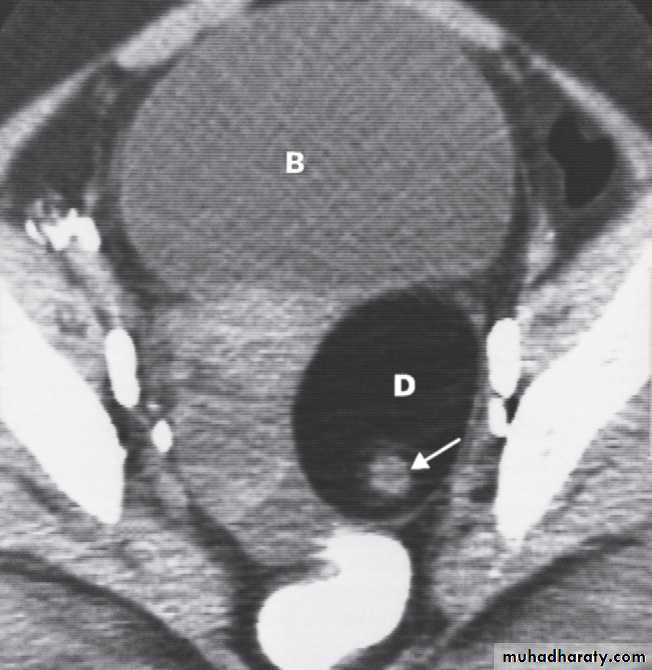

A dermoid cyst can usually be confidently diagnosed because of the fat within it, and it may contain various calcified components, of which teeth are the commonest.

These ovarian tumours are predominantly benign and can usually be recognized on ultrasound but are also readily diagnosed on CT or MRI and sometimes on plain radiographs .